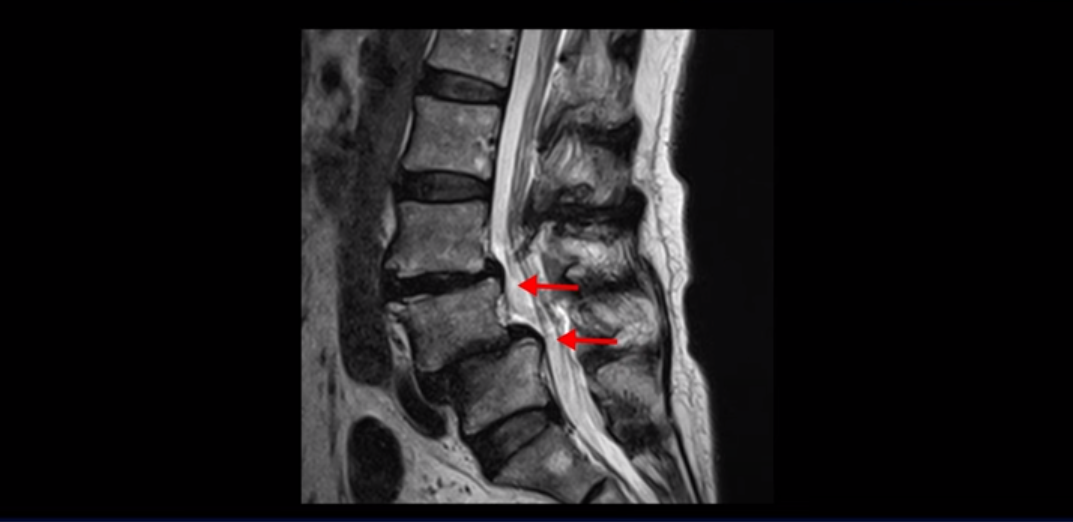

실제 저희 치료후기에 나오는 환자분들의 사례를 들어 설명해드리겠습니다. 이분은 전방전위가 2단계로 매우 심하고,

신경 구멍도 두 마디가 좁아져 있습니다.

전방전위와 협착이 다 심하니까 대학병원에서 나사 6개를 박는 유합술을 권유 받으셨는데요. 그런데 이분이 처음 아프게 된 건 작년 10월인데, 이분이 만약 아프기 전인 작년 초에 MRI를 찍었다면 지금의 MRI와 많이 다를까요? 아닙니다. 거의 차이가 없을 겁니다. 이미 척추 뼈는 많이 밀려나가 있고 신경 구멍은 똑같이 좁아진 상태였을 겁니다. 그 상태로도 전혀 안 아프게 아주 오랫동안 사신 겁니다. 그러다가 작년 10월에 무리한 일과 운동 때문에 허리 근육에 문제가 생기면서 신경이 눌리기 시작한 겁니다. 만일 아프지 않을 때 MRI를 찍고 척추 뼈가 밀려나가고 신경이 눌렸으니까 나사 박는 수술을 하자고 하면, 수술을 받을 사람이 있을까요?